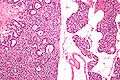

Micrographs of parathyroid adenoma